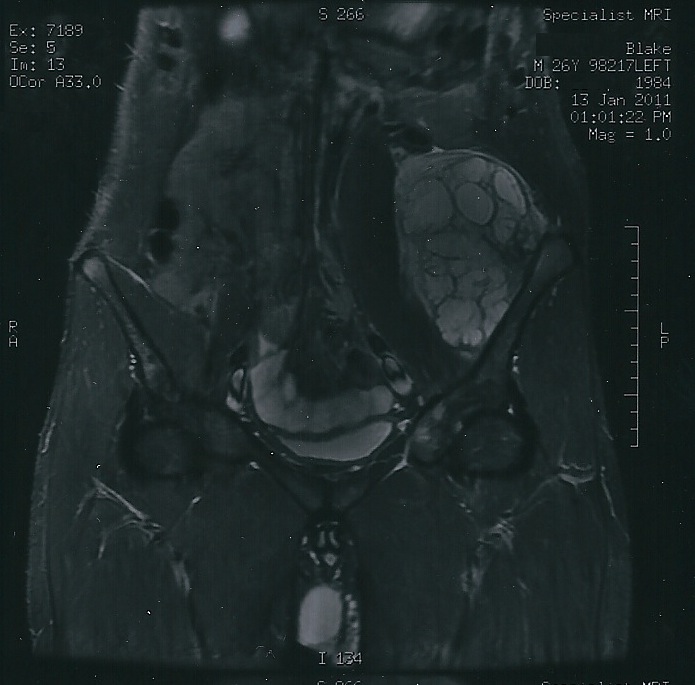

Giant Cell Tumor of the Bone

Giant cell tumor of the bone is composed of multinucleated giant cells and stromal cells that occur in young adults.

Giant cell tumor of the bone typically arises in the epiphysis of long bones, usually the distal femur or proximal tibia.

Radiology of giant cell tumor of the bone classically shows a “soap-bubble” appearance on x-ray.

Giant cell tumors of the bone are locally aggressive, and they may recur after surgical removal.